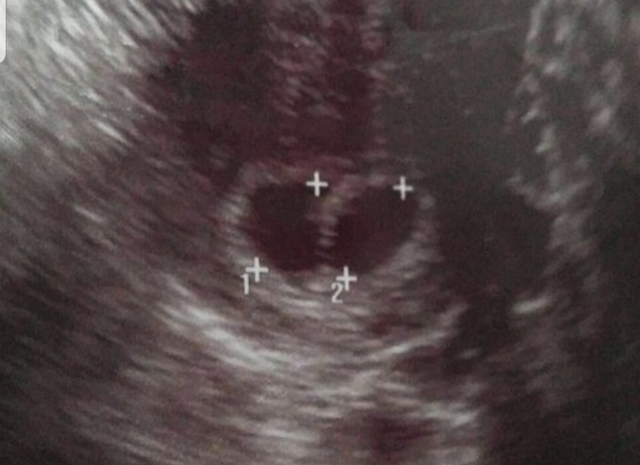

❤우리집쌍둥이아기시절👼👼❤